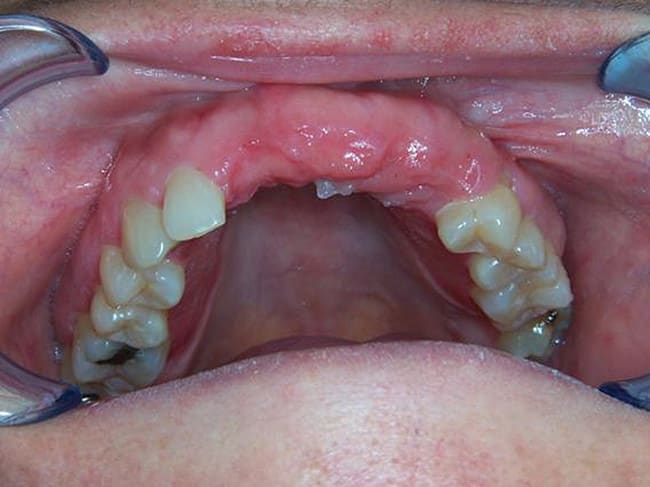

A panoramic roentgenogram or cone beam computed tomography scan was completed to assess bone parameters and plan implant placement sites. Consider the example of the stabilization of a maxillary and mandibular denture (Figure 1). The placement sites were marked on the radiograph between the canine and first bicuspid anterior to the mental foramen as well as in the region of lateral incisors anteriorly (Figure 2). Next, depending on the size and type of prosthesis, the quantity of mini implants to use was determined. The primary author recommends the placement of four mini implants for the stabilization of a full mandibular denture. While four mini implants may also be sufficient for a maxillary denture stabilization procedure, six are recommended if a palateless denture is being considered. For single tooth replacement one mini implant is used for anterior and bicuspid teeth, while for molars, often two mini implants are used.12,13 In this context, occlusal and masticatory forces are distributed over an augmented implant interface; the relative strain on any implant is reduced.13 Furthermore, the bridgework in these cases acts as a splint, anchoring adjacent implants and reducing micro-movement.13 Similarly, adjacent missing teeth replaced using mini dental implants should be splinted together.

The pilot hole for the mini implants was then made using a 1.2-mm pilot drill (approximately half the diameter of the mini implants). Using sterile surgical techniques17 the dentist drilled to the appropriate depth based on bone density evaluation and implant type selected. For very dense bone, a pilot hole was drilled to be 80% of the length of the implant. For moderately dense bone, the pilot hole depth was 60% of the length of the implant. For low-density bone (maxillary bone or soft mandibular spongy bone) the pilot hole was created at 50% the length of the mini implant. Because of the flapless surgical technique most often utilized with mini implants, a surgical stent (Figure 5) designed from preoperative dental models, x-rays, and/or cone beam CT scans provides for proper angulation in the bone. A pilot drill guide (Figure 6) was used to position the pilot hole in the center of the surgical stent sleeve and maintain correct trajectory of the drill.18,19 The pilot drill was used to puncture the tissue down to the bone, and after locating the bone surface the pilot hole was made with a tapping motion.

The mini dental implants used in this study were inserted such that the square neck portion of the implant was supragingival. O-ring housing abutments were then placed on the O-balls of the mini implants (Figure 8). With a pear-shaped laboratory bur, holes were placed in the patient’s denture at the previously marked locations. The denture was tried in the patient’s mouth for full seating. The holes in the denture were then filled with a housing resin or cold-cure acrylic. Before these materials set, the denture was placed on the O-ring housings and seated firmly. The patient was instructed to bite down for 3 to 5 minutes. The denture was then removed and the firmness of the housings was assessed. If housings were loose, the appropriate acrylic was applied. The denture with housings was then smoothed and adjusted to avoid patient discomfort and sore spot development (Figure 9). A postoperative radiograph can be seen in Figure 10.